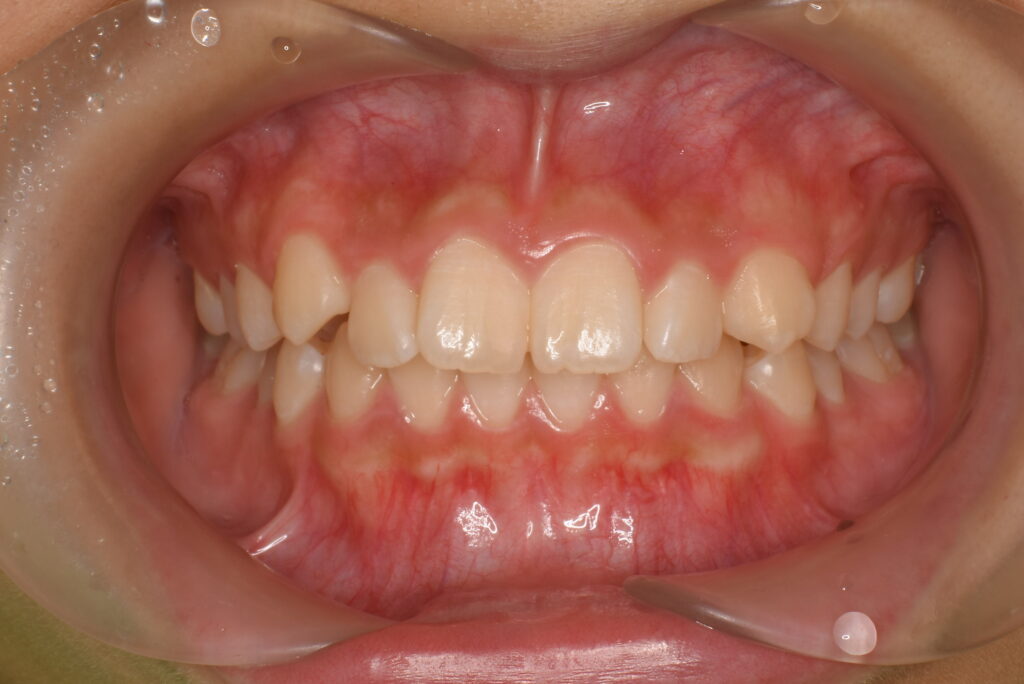

• BEFORE

患者様は、歯のガタつき(叢生)や不揃いな歯並びを気にされて来院されました。

また、食べ物が歯の間によく詰まることも不快感につながっており、改善を希望されました。

目立ちにくい装置での治療を希望され、マウスピース型矯正(インビザライン)を選択されました。診査の結果、インビザラインによるマウスピース矯正を実施しました。

歯列全体を整えることで、叢生(歯のガタつき)の改善と咬合のバランス回復を図りました。